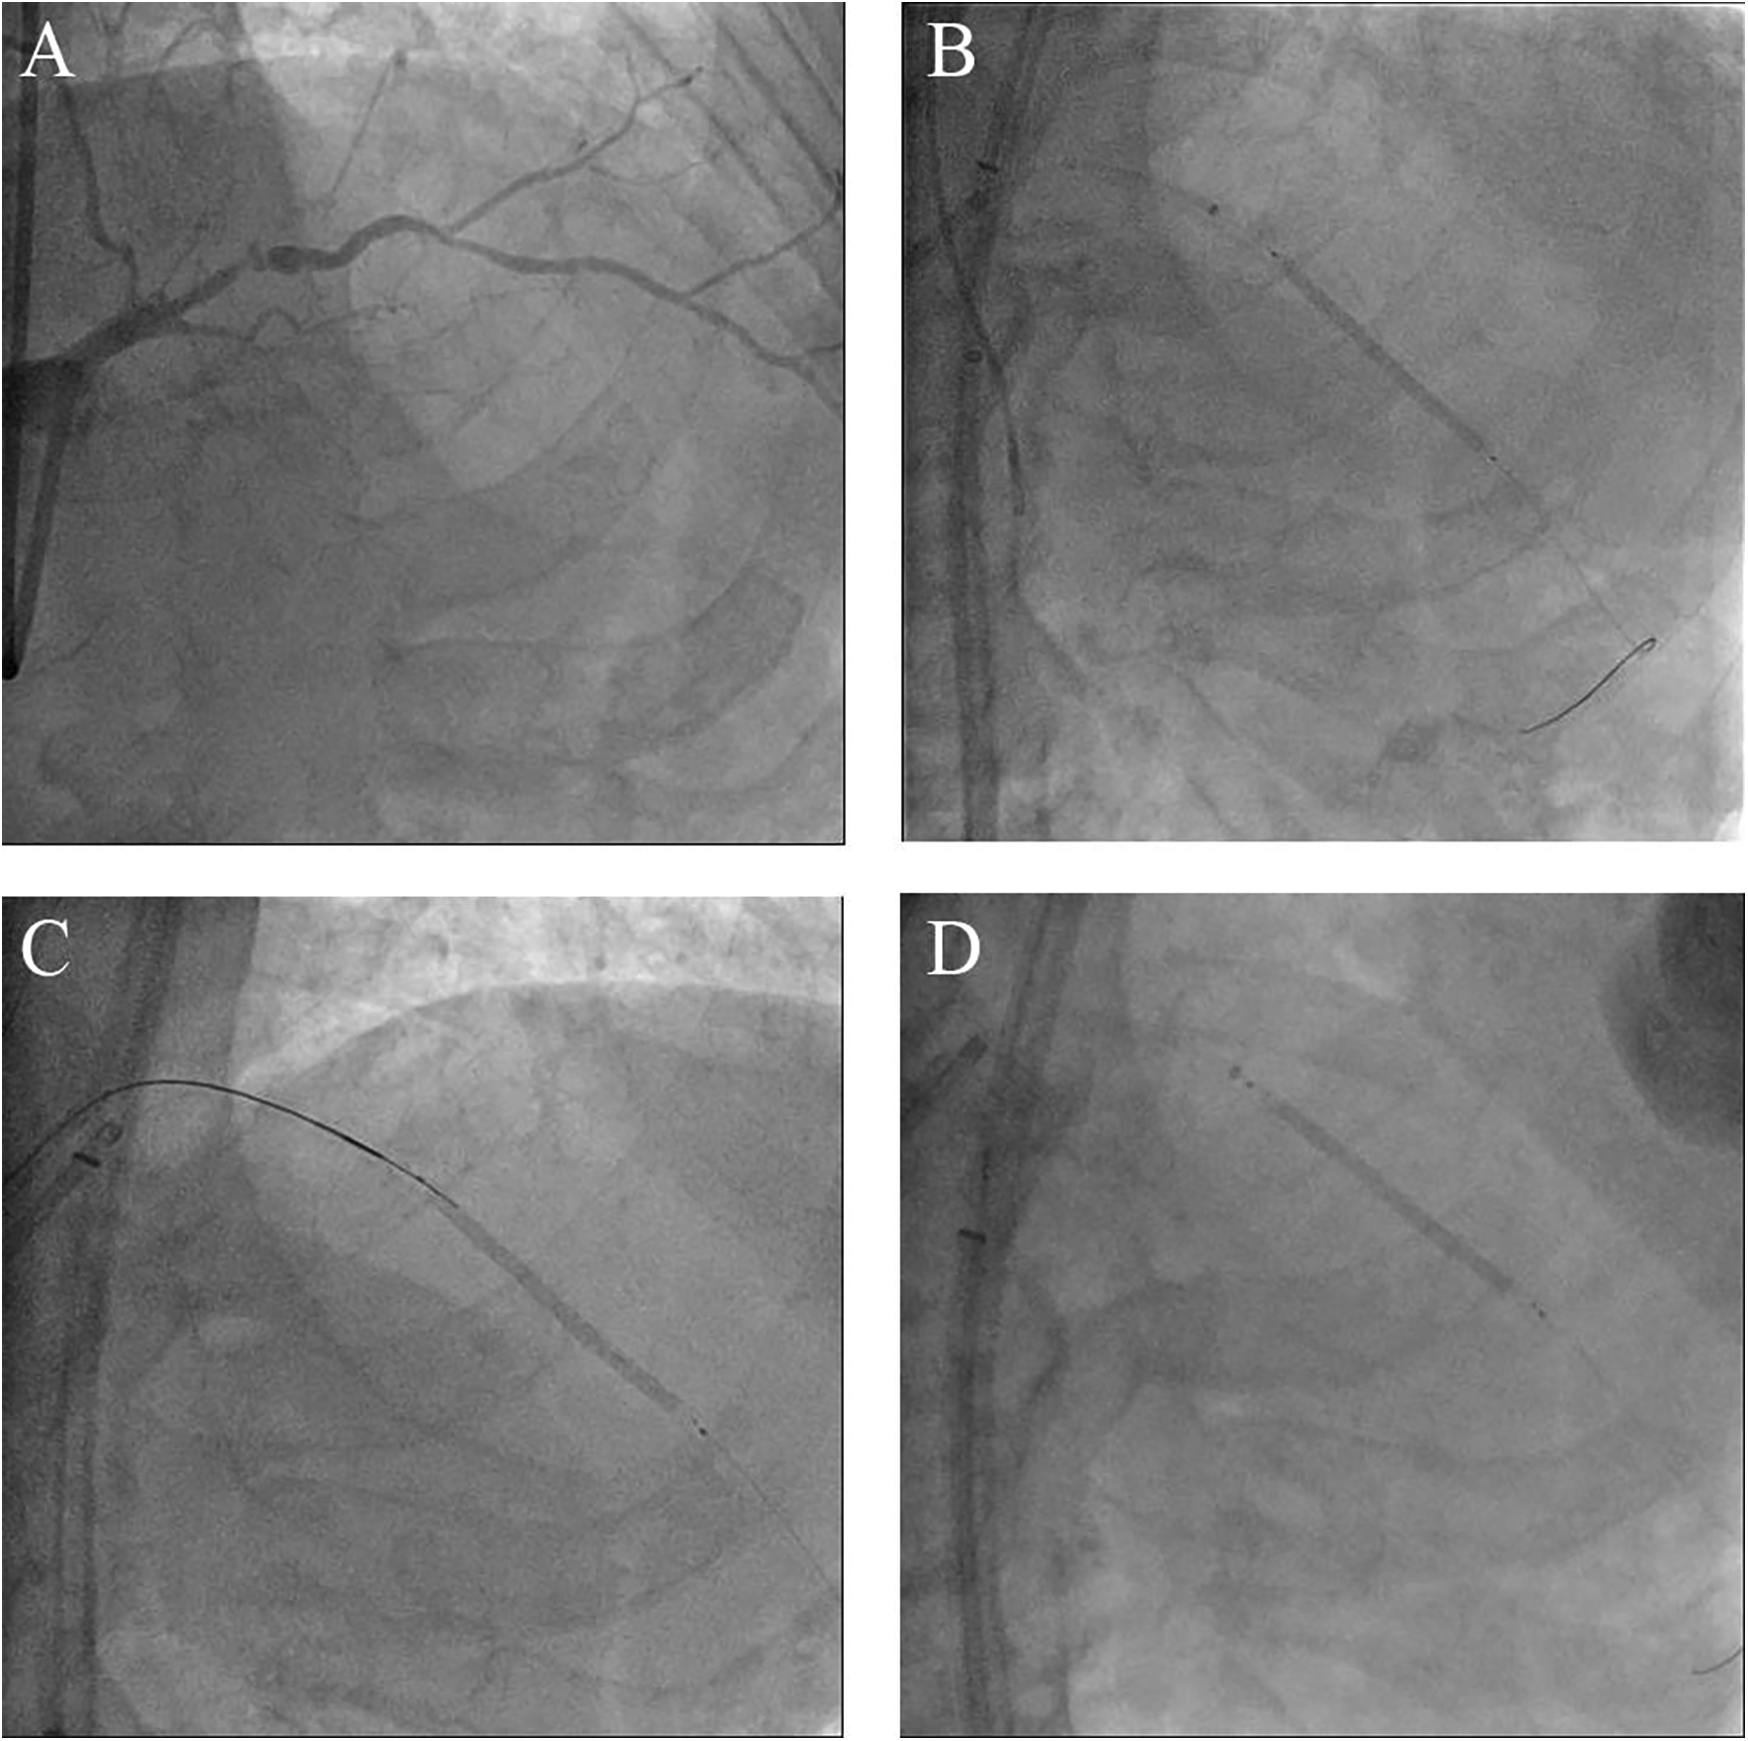

Figure 1

Morphology of the coronary lesions and several attempts to manage the undeflatable coronary balloon. (A) Coronary angiography from right anterior oblique cranial projection showing a CTO-like lesion of the proximal LAD. (B) Failure to deflate the stent balloon despite strong negative pressures using a saline-filled indeflator. (C) Attempt to perforate the undeflatable balloon using a stiff wire with microcatheter support. (D) Attempt to pull the undeflatable balloon back after deep intubation of the guide extension catheter; CTO, chronic total occlusion; LAD, left anterior descending artery.

Coronary angiography, performed as part of an early invasive strategy, revealed a severely calcified chronic total occlusion (CTO)-like lesion in the proximal LAD and calcified stenosis of the ramus intermedius branch (Figure 1A). Right coronary angiography showed no significant stenosis, with CC grade 1 collaterals supplying the LAD via the epicardial and septal vessels. During two days of diuresis and stabilization, the patient's chest pain and dyspnea improved, and no dynamic ST-segment changes were observed. On day 3, PCI was performed according to the patient's preference. The laboratory findings on the day of PCI showed CK-MB 82 ng/ml and high-sensitivity Troponin I 13,138 pg/ml. Both common femoral arteries were accessed for PCI. An 8 F EBU 3.5 guiding catheter (Medtronic, Minneapolis, MN, USA) was used to engage the left main ostium. The LAD was successfully wired using the antegrade wire escalation technique, a commonly used approach in contemporary CTO PCI. (Escalation from Sion BLUE (Asahi Intecc, Japan) → Fielder XT-R (Asahi Intecc, Japan) → Ultimate Bros 3.0 (Asahi Intecc, Japan), with Corsair Pro XS (Asahi Intecc, Japan) microcatheter back-up.) 7F Guidezilla™ extension catheter (Boston Scientific, Natick, MA, USA) was introduced, and lesion preparation was sequentially performed using a 2.0 mm semi-compliant balloon followed by a 2.5 mm non-compliant balloon. Intravascular ultrasound confirmed the wire was in the true lumen throughout the LAD, revealing diffuse and calcified stenosis from the proximal to the distal LAD. Subsequently, a 2.5 × 46 mm Cre8™ EVO (Alvimedica, Istanbul, Turkey) drug-eluting stent (DES) was delivered and positioned across the mid-LAD lesion without resistance. During stent deployment, the dial on the pressure gauge window did not rise appropriately despite multiple adjustments to the indeflator handle. After approximately 15 attempts, we reached the rated burst pressure of 18 atm, achieving full stent balloon expansion (Figure 1B). However, retraction of the handle failed to deflate the balloon. Despite the dial indicating zero pressure and a strong tactile sensation of negative pressure when pulling back the handle, the stent balloon remained inflated with no signs of deflation. Our initial suspicion was a malfunctioning indeflator device. Therefore, we immediately switched to a new indeflator, filling the column with normal saline alone to dilute the contrast/saline mixture in the balloon catheter through slight inflation followed by full deflation. However, this also failed to deflate the balloon. We then attached a three-way stopcock connected to a 50 cc syringe to the balloon catheter and applied strong negative suction, but this also proved unsuccessful. After all efforts to deflate the balloon using negative pressure failed, we decided to attempt intentional balloon perforation using a stiff guidewire. A 7 F Judkins Left 4 (JL 4) guide catheter was inserted via the left femoral artery. The first EBU guide catheter was slightly withdrawn, and the JL 4 guide catheter was advanced into the left main. A Turnpike® LP microcatheter (Teleflex, Wayne, PA, USA) was used to deliver the wire. We attempted to puncture the inflated balloon with both the distal and proximal end of a Conquest Pro 12 and Astato® XS 20 wire (Asahi Intecc, Japan) multiple times (Figure 1C), but these attempts were unsuccessful. As the next step, we advanced the GuideZilla™ guide extension catheter deeply and attempted forceful retraction of the trapped stent balloon, which again failed (Figure 1D). Meanwhile, the patient developed severe chest pain and ST elevation on the electrocardiogram monitoring. His hemodynamic status deteriorated, necessitating the initiation of norepinephrine and dopamine. We contacted the cardiothoracic surgeon to discuss surgical options. To avoid delays in this critical patient, we decided to attempt ultra-high-pressure inflation of the balloon beyond its rated burst pressure as a last interventional resort. At 23 atm, the pressure dial suddenly dropped, and the contrast dissipated from the balloon, indicating a rupture (Figure 2A). The balloon was then successfully retrieved into the guiding catheter and removed from the coronary artery (Figure 2B). However, follow-up angiography revealed multiple Ellis grade III perforations in the stented LAD segment (Figure 2C). A 2.5 mm semi-compliant balloon was immediately inflated in the mid-LAD to plug the perforation. Despite prolonged inflation for 15 min, the perforation remained unsealed, necessitating the deployment of 3.5 × 19 and 2.8 × 19 mm GraftMaster covered stents (Abbott Vascular, Santa Clara, CA, USA) in the proximal and distal segments of the stented LAD using the Ping Pong technique (Figures 3A,B). As the patient's hemodynamic status remained unstable, an emergency pericardiocentesis was performed. Angiography still showed persistent extravasation in the mid-segment of the stented LAD, so an additional 2.8 × 19 mm GraftMaster covered stent was deployed (Figure 3C). After successfully managing the coronary perforation, a 3.0 × 33 mm DES was placed in the stenotic proximal LAD, followed by post-dilation with a 3.5 mm non-compliant balloon. Final angiography confirmed well-expanded stents with no dissection or residual perforation (Figure 3D). Fortunately, the patient was discharged after 19 days (including three days in the intensive care unit) and remained asymptomatic for two months. We initially planned to place him on lifelong dual antiplatelet therapy, but he was later transferred to an elderly care hospital and lost to follow-up.